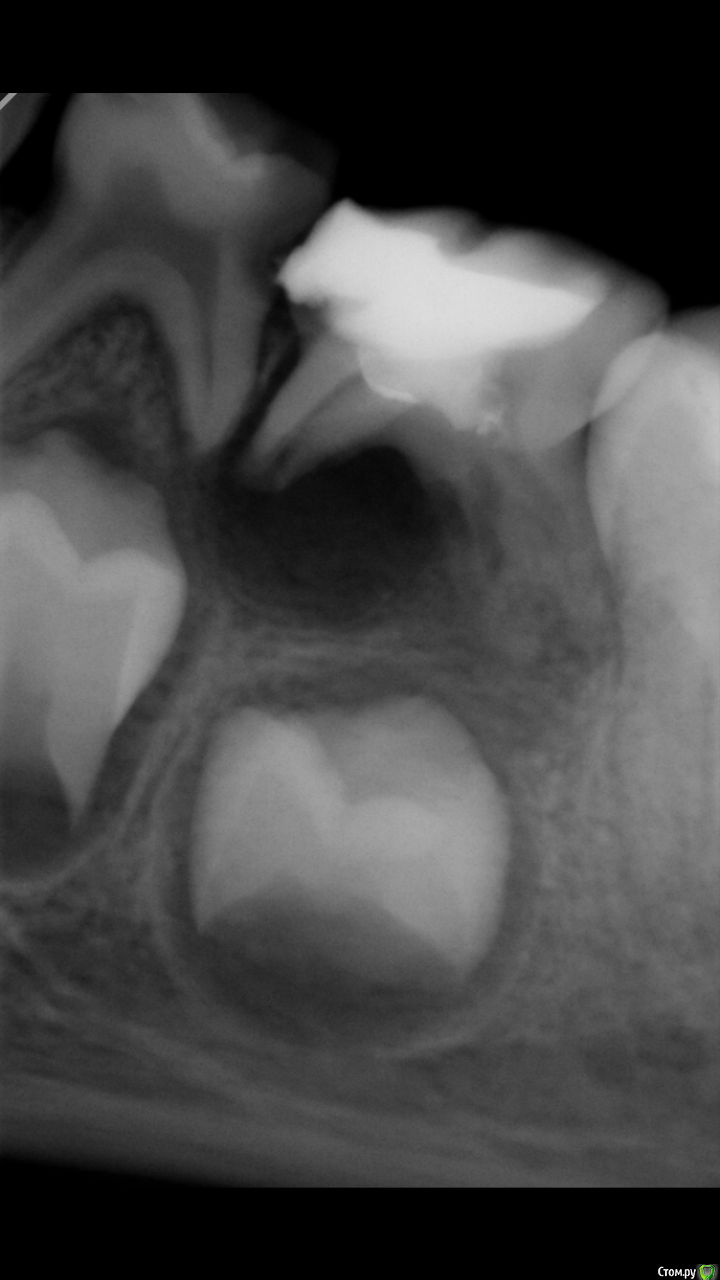

Усина Опубликовано 22 марта, 2018 Поделиться Опубликовано 22 марта, 2018 (изменено) Коллеги, подкажите как часто сталкивались с иволюцией зачатка постоянного зуба?тактика ведения таких больных?девочка 7,5 лет пришла с радиксом 8.4 зуба, на диагностическом снимке обнаружено инволюция зачатка постоянного зуба(8.5-лечен рф- методом)надо ли удалять 8.5? Изменено 22 марта, 2018 пользователем Усина Ссылка на комментарий

Усина Опубликовано 3 апреля, 2018 Автор Поделиться Опубликовано 3 апреля, 2018 Спасибо за совет!!!сравните развитие 4.4 и 4.5- мне кажется, мало вероятно, что 4.5 сформируется!на курсах А.Гецман рассказвала о инволюции зачатка постоянного зуба, думаю здесь именно это и происходит Ссылка на комментарий